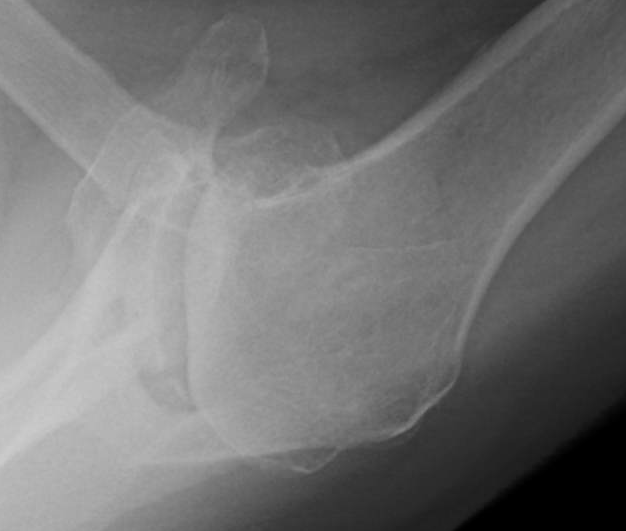

Shoulder Arthritis / Rotator Cuff Tears causes of shoulder pain X